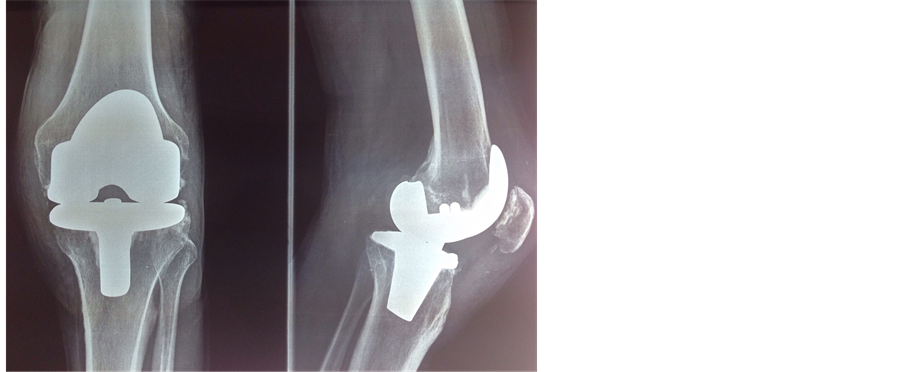

A 73-year-old man consults in our structure for persistent pain and deformation of the lower left leg at the knee for three months after a traffic accident. The patient presents a wound in his left knee that was sutured in the emergency without any radiological assessment; He couldn’t walk or stand for 3 months. Physical examination revealed a deformed left knee in bayonet with antero-posterior enlargement (Figure 1) and a passive flexion of 30˚ and 30˚ to 150˚ of motion without frontal laxity (Figure 2). The extensor mechanisms and the neurovascular functions were all intact. Radiographically, the left knee showed an unreduced posterior dislocation (Figure 3). After detailed explanations of the risks and benefits, a TKA of the left knee was performed. A midline incision using the conventional medial parapatellar approach to the knee was made. Intraoperative examination revealed a fixed posterior dislocation of the knee, and missing osteochondral surfaces over the lower part of the femoral trochlea and anterior tibia plateau and both anterior and posterior cruciate ligaments were absent (Figure 4) with contracture of the posterior soft tissues. Medial-lateral soft tissue balancing was performed first, followed by classical bony cuts at 6˚ anatomical axis. A normal femoral component was chosen after a posterior soft-tissue release for balancing the flexion-extension gaps (the release was not important in the fear to touching the vascular axis). The patella was resurfaced, and posterior soft-tissue release was carried out extensively to allow full extension of the left knee with the components being tested in position. Flexion-extension and medial-lateral gaps were also checked to be nearly in balance, with relative stability during the full range of motion with the prostheses in place. Because stability was obtained using an LPS (Legated postero stabilized) type of implant. A constraining implant was not considered necessary. Finally, Nexgen Fixed-Flex total knee components (LPS type, Zimmer) were applied and fully cemented (Figure 5). The intraoperative range of motion was approximately―10˚ - 160˚ a posterior splint was applied to prevent a dislocation for 4 weeks. No dislocation has been noted and mobility was started in the fifth week without complication. At latest follow-up 1 year postoperatively, the man had a stable left knee with a range of motion of―10˚ - 120˚ and Lysholm à 80. Radiographs showed a well aligned and well fixed total knee prosthesis (Figure 6). The patient was very satisfied with the final outcome.

Figure 5. Nexgen Fixed-Flex total knee components (LPS type, Zimmer) fully cemented.

Figure 6. Radiographs showing a well aligned and well fixed total knee prosthesis.